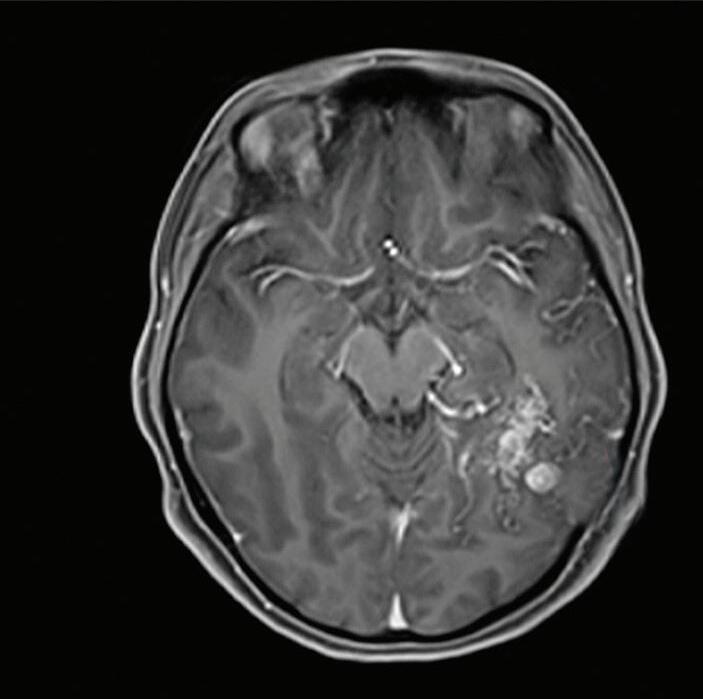

Fig. 1-20. RNM T1 com contraste em cortes (a) axial e (b) sagital e (c) FLAIR axial, demonstrando MAV do giro fusiforme esquerdo com presença do aneurisma pós-nidal (setas azuis). Angiografia pré-operatória em (d) AP e (e) em perfil mostrando a MAV anteriormente descrita, nutrida por ramos da artéria cerebral média e posterior esquerda, com drenagem superficial para o seio transverso e sigmoide ipsilateral e aneurisma pós-nidal venoso (setas azuis). (f) Visão intraoperatória do aneurisma pós-nidal (seta azul).